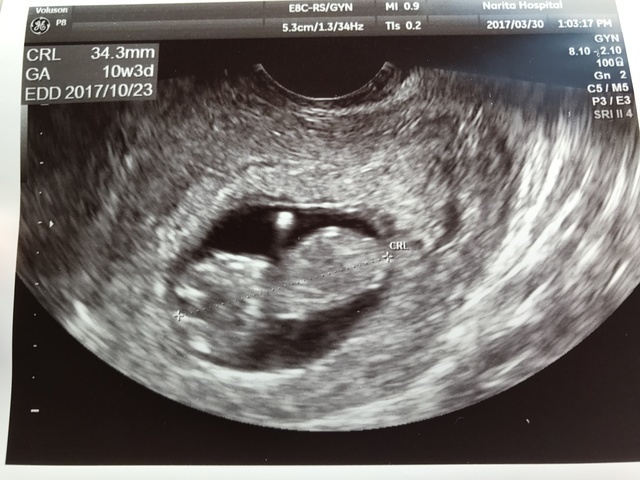

10週3日(10w3d・男の子)|りくえもん さん(32歳)

エコー写真撮影時のエピソード:

チョコレート嚢胞を患い、自然妊娠は難しいと言われ、体外受精を行なっていました。

昨年の秋に7週で稽留流産を経験し、今回上手くいかなかったら、嚢腫摘出手術をすると決めて挑んだ移植で、無事心拍確認ができました。

ただ、前回のこともあり、胎嚢確認ができても心拍確認ができてもまだまだ不安でしたが、このエコーで手足をもぞもぞさせて元気に動いている姿を確認し、やっと安心できました。